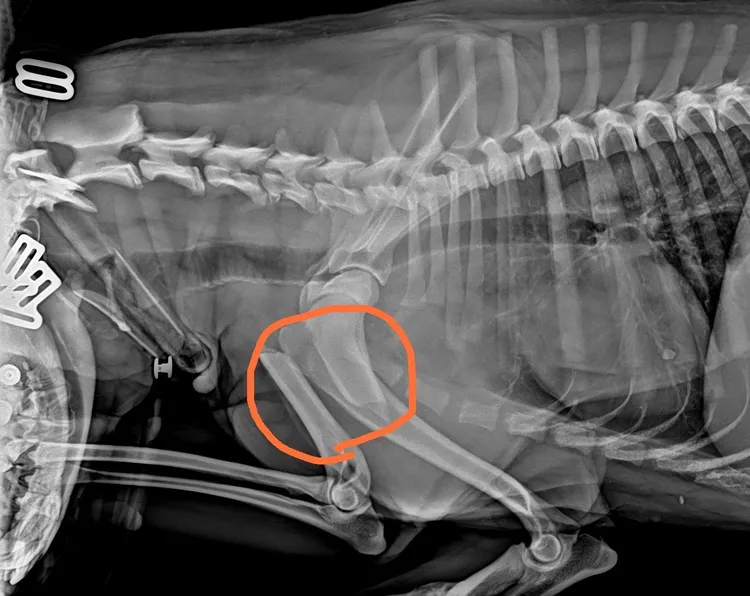

動保處獸醫師李建沛表示,依照醫療中心傷病動物案例研究,狗的車禍骨折最常發生在大腿骨或是小腿脛骨,前肢骨折也有但比後肢少,這隻狗上臂骨折挫位嚴重,幸好即時送醫手術治療,才能免除跛腳的危險。